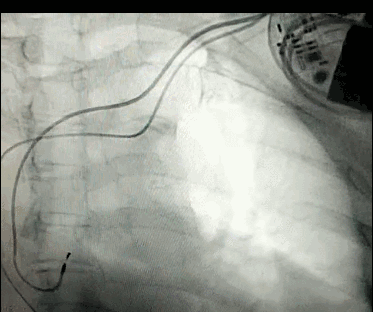

腦血管成像的“金標(biāo)準(zhǔn)”!——DSA三部曲之技術(shù)篇

DSA是將造影劑注入需要檢查的血管中,使血管顯露原形,然后通過系統(tǒng)處理,使血管顯示更加清晰,便于醫(yī)生診斷或進(jìn)行手術(shù)。